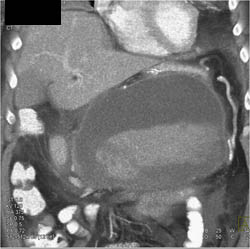

Pseudocyst Compresses Splenic Vein